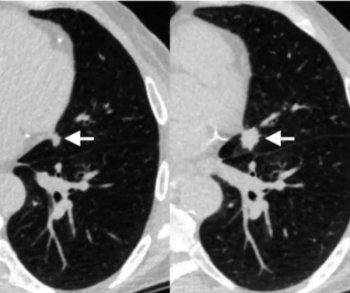

Performing computed tomography pulmonary angiography (CTPA) with a high-pitch photon counting detector (PCD) offers enhanced signal-to-noise ratio (SNR) and contrast-to-noise ratio (CNR) at a reduced radiation dose in comparison to employing an energy-integrating detector (EID), according to new research.